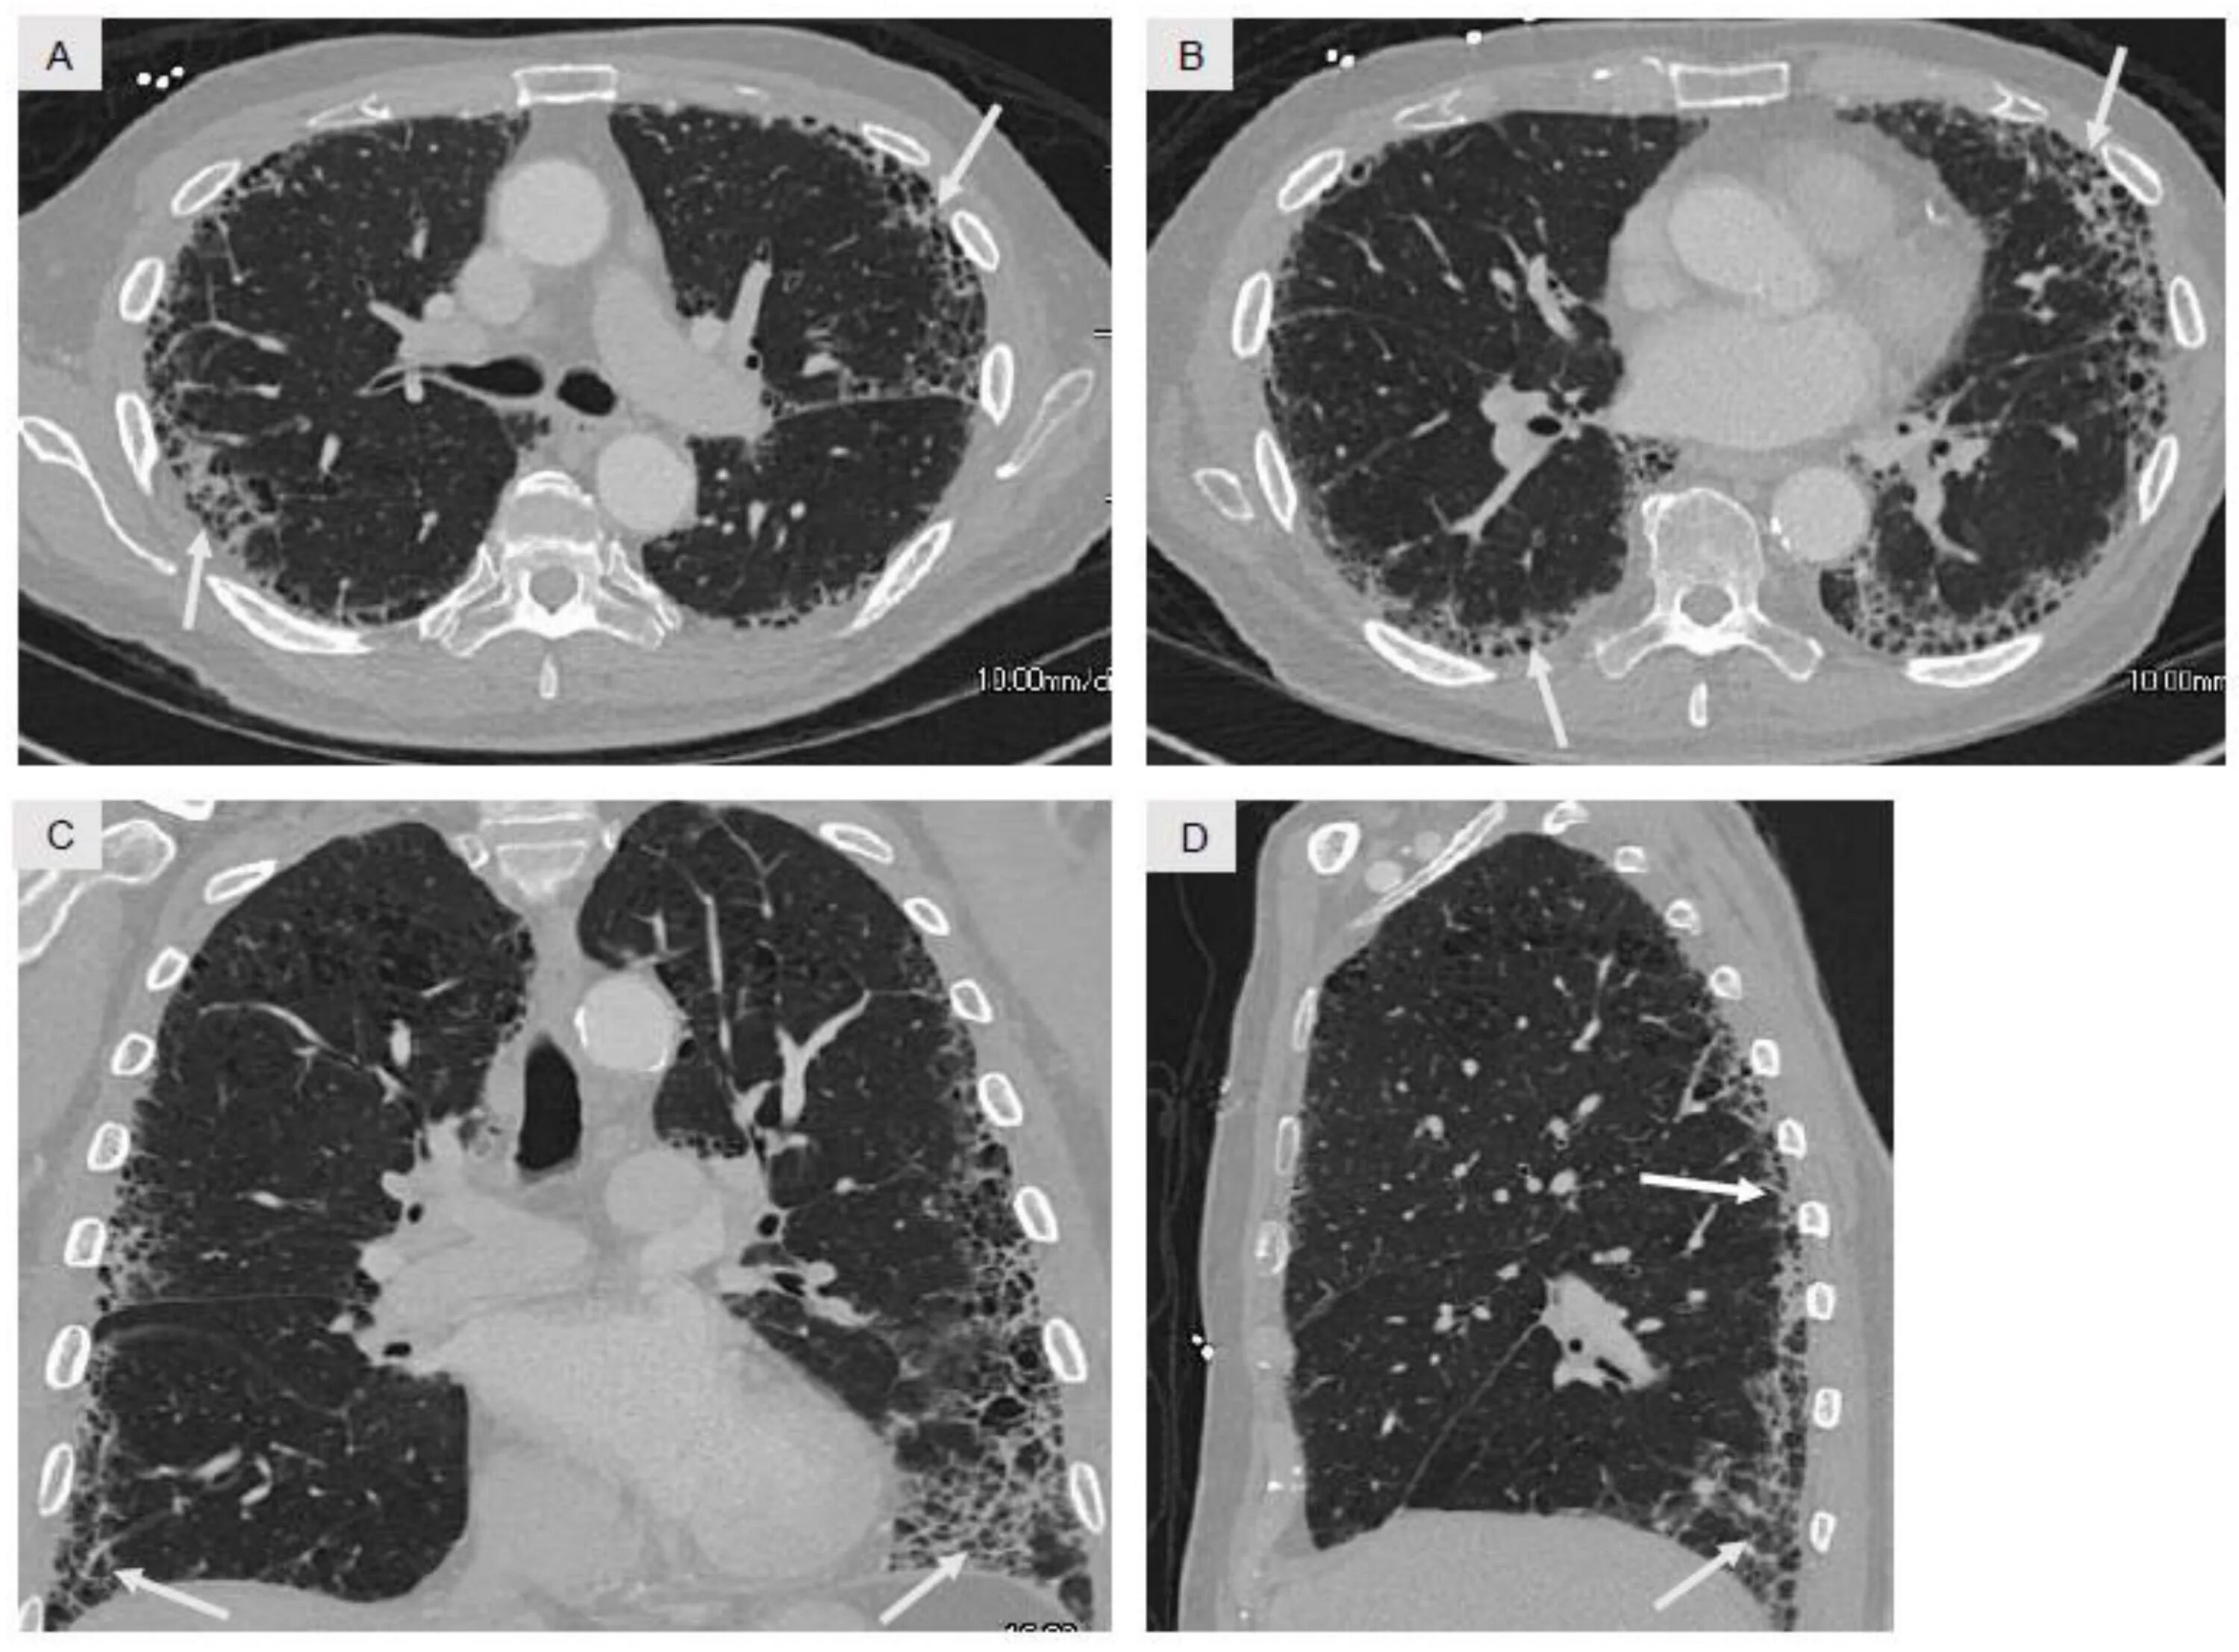

Кт х